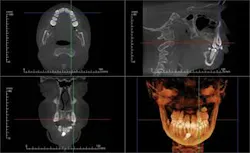

Dolphin Imaging® (dolphinimaging.com) and InVivoDental by Anatomage® (www.anatomage.com) are two software developers who are on the cutting edge of software for orthodontic and orthognathic treatment-planning and archiving. Both packages offer conventional cephalometric analysis based upon digitized 3-D volume renderings. The soft tissue and facial photos (in 2-D or stereographic formats via 3-D MD camera system) can be superimposed and phased in over the skeleton with a translucency feature. This feature enables integrated dento-facial analysis showing how the soft tissues are influenced by dento-skeletal positions. Location, size, and density of lesions and bone cysts — as well as positions impacted and supernumerary teeth — can be rendered in 2-D and 3-D to help determine the best approach for surgical access. (Figure 2).

CBCT images can be modeled by Anatomage in the traditional form of digital study casts. They can then be viewed and morphed into desired tooth positions. The pre/post treatment CBCT scans can be superimposed showing the positional change between the two, which is actually 4D imaging (Figure 3). An animated, digital morph movie can be made to show the before and after morphing.